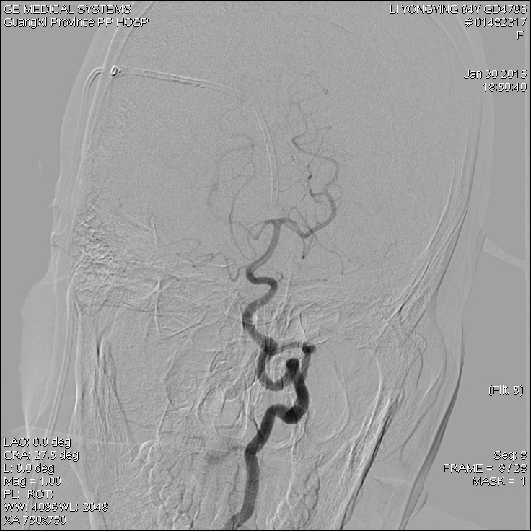

2015-1-30 DSA